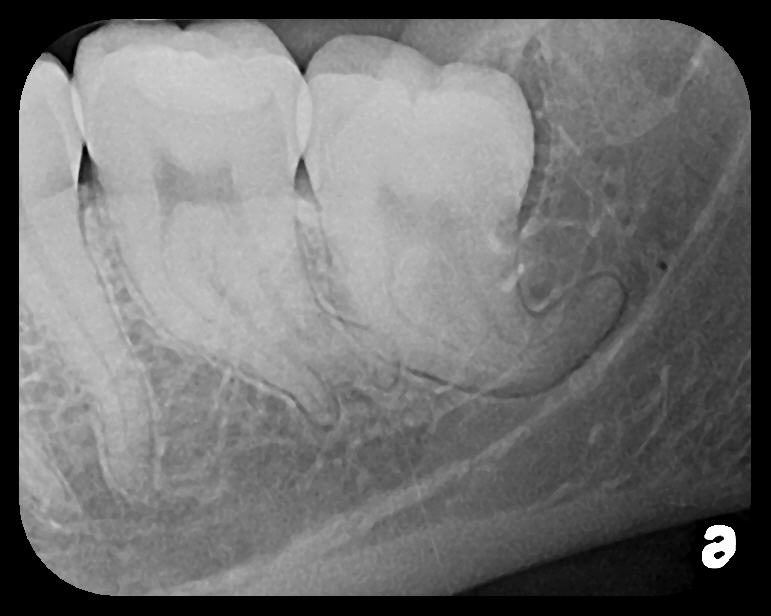

Fig 3. Two PSP PA radiographs of mandibular teeth showing: left, the initial view

of molar area and suspected pathology surrounding impacted tooth No. 32; center,

subsequently exposed PA radiograph, placed more distally, demonstrates extent

of large cyst as well as entire tooth and root No. 32. Proper alert as to presence

of suspected cyst and appropriate referral for 3D CBCT study and surgical

enucleation was given to the patient. Right: Same radiograph as on the left, but

with lighter superimposed outline of the area that would be visible using an HW

sensor rather than a PSP sensor. The small area of pathology is likely obscured

because it is visually overlaid by the root of tooth No. 31. Neglect of this significant

pathology may have resulted.

Figure 3